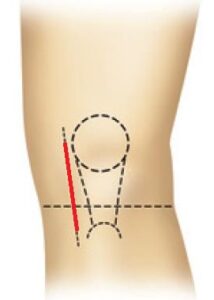

- Τομή περίπου 5 εκατοστών (εικόνα 8 και εικόνα 9 )